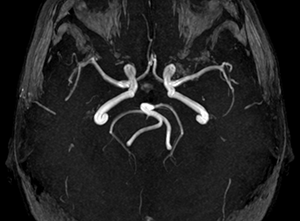

Развитие Виллизиева круга

Виллизиев круг — система церебральных артерий, расположенных в области основания головного мозга. Она компенсирует дефицит кровотока с помощью дополнительных сосудистых бассейнов. Патологическое развитие виллизиева круга может стать причиной формирования заболеваний. Рассмотрим основные методы диагностики патологий.

МР-ангиография. Врач получает детализированные изображения сосудов головного мозга без применения рентгеновского излучения.

КТ-ангиография. После внутривенного введения контрастных веществ выполняется сканирование с получением трехмерной модели анатомической структуры.

Виллизиев круг на диагностическом снимке

МР-ангиография — один из наиболее дорогостоящих, но, вместе с тем, и довольно информативный способ диагностики строения Виллизиева круга. Она проводится в магнитном томографе и противопоказания к ней такие же, как для обычной МРТ (высокая степень ожирения, клаустрофобия, наличие в организме металлических имплантов, проводящих магнитное поле).

МР-картина показывает строение сосудов Виллизиева круга, наличие или отсутствие соединений между ними, аплазию или гипоплазию артерий. При оценке результата специалист может определить диаметр каждой артерии и особенности ее ветвления.

Видео: пример МР-ангиографии мозга

(Виллизиев круг замкнут; определяется извитой S-образный ход интракраниального отдела левой позвоночной артерии; С-образный ход основной артерии; в остальном, в сегментах ВСА и парных артерий кольца основания мозга данных за наличие гемодинамически значимых стенозов, патологических извитостей не получено).